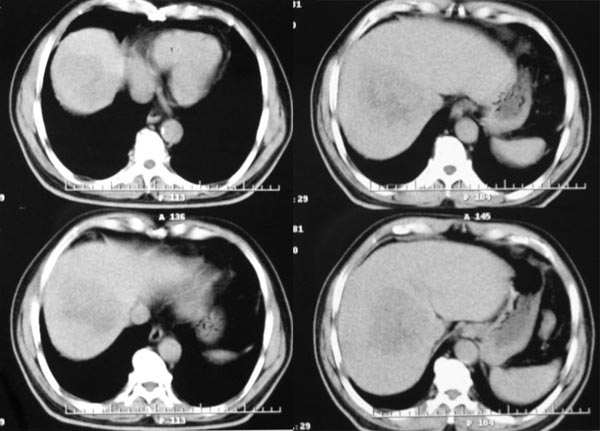

患者,m,71y,乏力、纳差、巩膜黄染两月余,b超示肝内占位性病变。

平扫

1.临床资料:71y,乏力、纳差、巩膜黄染两月余。

2.病灶特点:平扫呈低密度,密度不均,中央呈更低密度;动脉期病灶周围强化较明显,高于正常肝组织,低于同层主动脉密度,中央坏死区未见明显强化;门静脉期,病灶呈低密度,低于正常肝组织密度。

3.诊断:符合肝细胞癌。

病灶特点:1、平扫:肝右叶大片状低密度影,内见更低密度影,边界不清